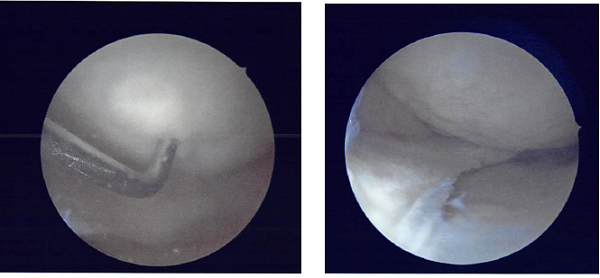

Final pictures were taken and saved. The knee was irrigated thoroughly and drained. The arthroscope was removed. The closure was performed using #4-0 Vicryl and #3-0 nylon.